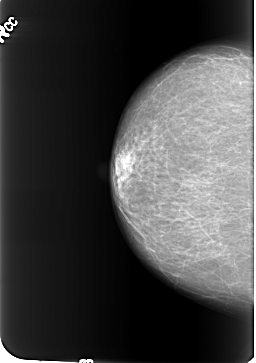

B_3233_1.RIGHT_CC

RIGHT_CC LINES 5440 PIXELS_PER_LINE 3832 BITS_PER_PIXEL 12 RESOLUTION 50 NON_OVERLAY